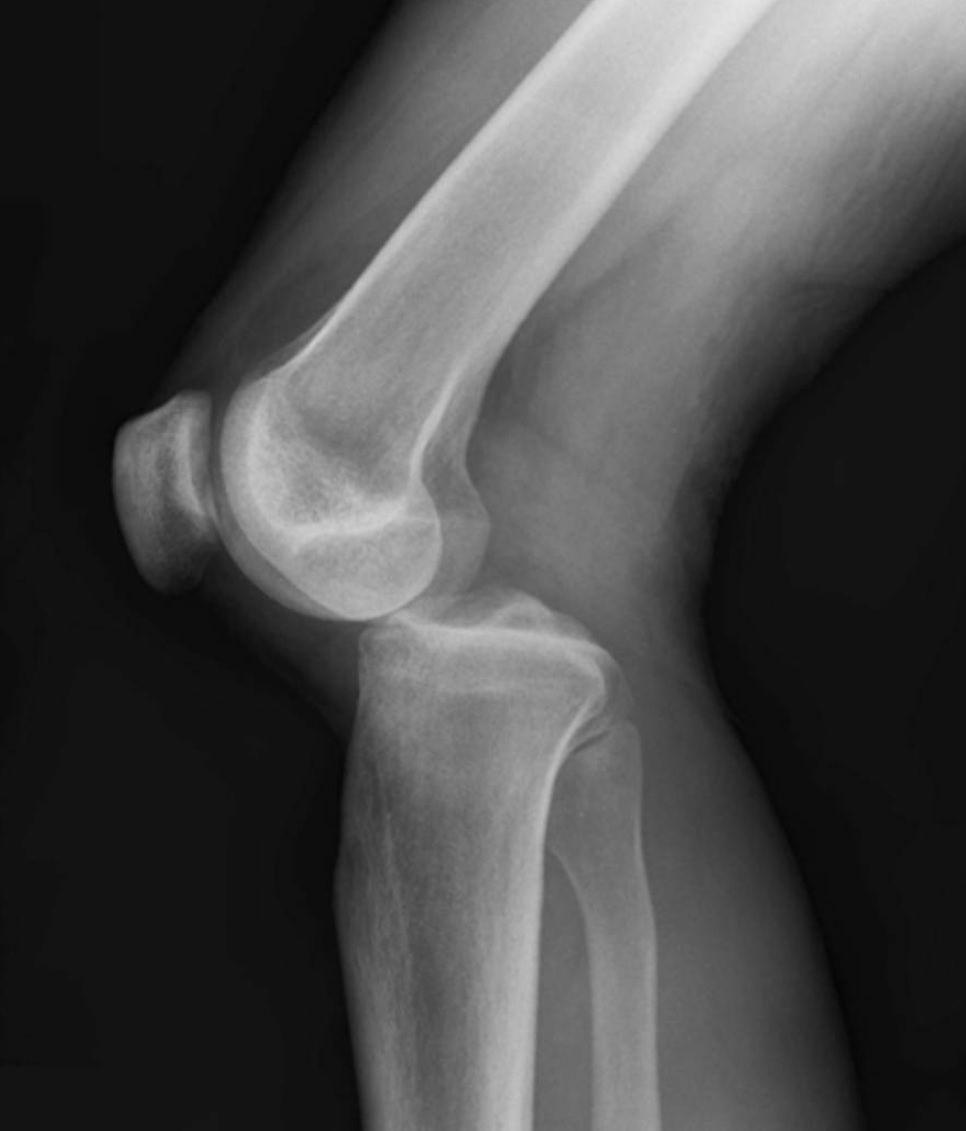

This injury can result from a blow or twist to the knees from improper landing after a jump or from running too hard without warm-up.

Knee Injuries